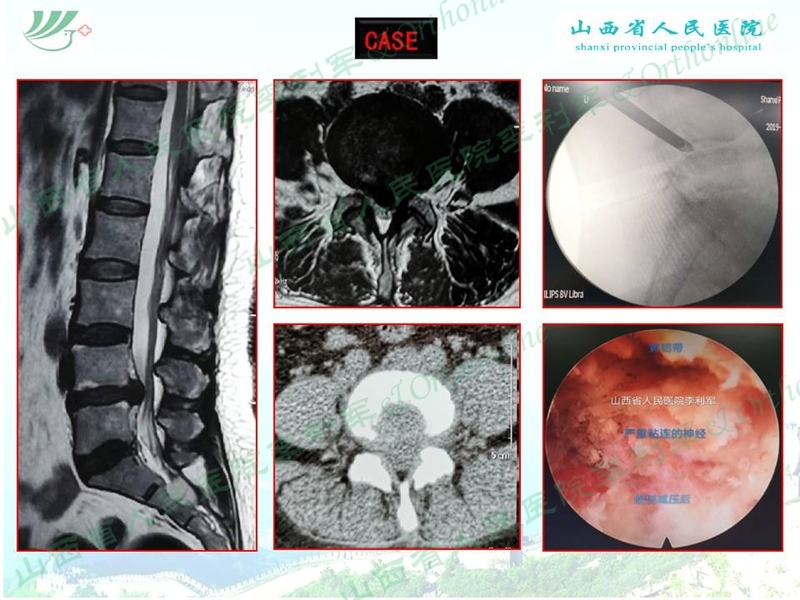

山西省人民医院李利军医生根据自己临床遇到的部分病例,归纳常见的特殊腰椎间盘突出为:高度游离间盘突出,伴有钙化的间盘突出,巨大间盘突出,复发间盘,极外侧间盘突出,易误诊为肿瘤的间盘突出,伴有神经变异的间盘突出等;并根据自己的临床体会对以上特殊类型间盘突出的孔镜治疗作了一些技术总结,以期达到抛砖引玉的作用,并等到大家的批评和指导。

椎间孔镜治疗特殊类型腰椎间盘突出症